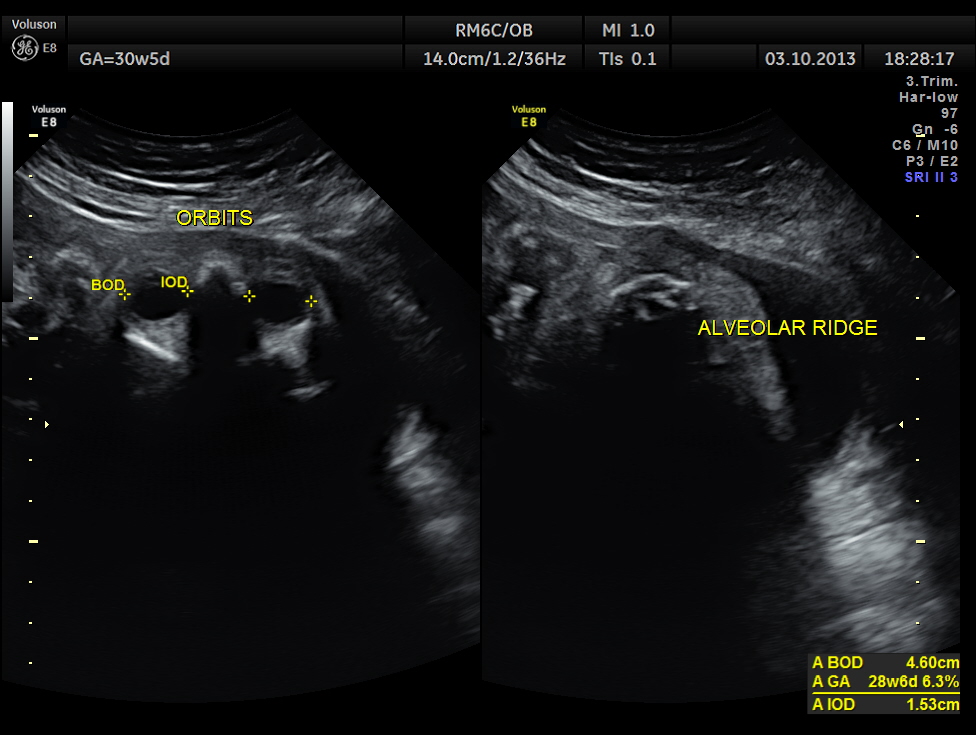

BPD AND HC < 2.3 % TILE suggestive of microcephaly. AC 6.2 % TILE suggestive of growth restriction.

The cerebellum shows 32.1 % tile growth.